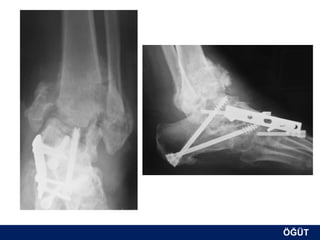

OLGU No 5   H.G., 26y, K

ÖĞÜT

Postop 3. ay

Postop 6. ay